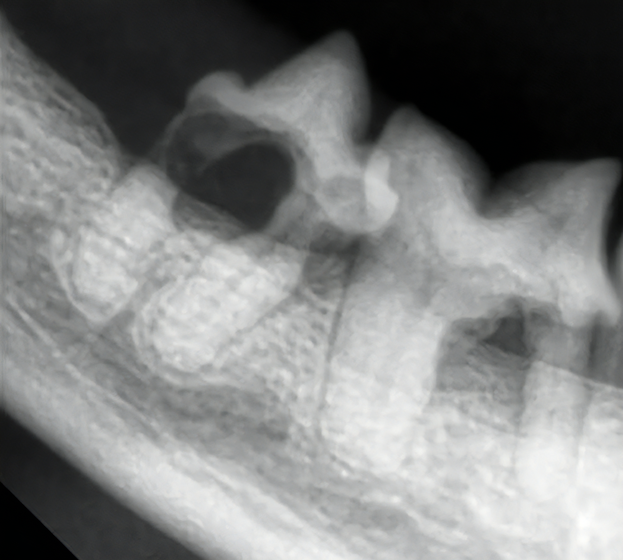

変形性脊椎症は、身体を支えている背骨(脊椎)が年齢とともに少しずつ変形してしまう病気です。多くは無症状なためレントゲン検査で偶然見つかることも珍しくありません。しかし、変形した脊椎が神経を圧迫することで痛みや歩行異常が現れることがあります。椎間板の変性や加齢による椎体間の不安定性が原因と考えられています。症状が見られる場合は、鎮痛剤で痛みを和らげたり、温熱療法などの理学療法で筋肉の緊張をほぐしながら経過を見ていきます。最近活動量が減ってきた、歩きにくそうにしている、などの変化は病気のサインかもしれません。なにか気になる症状があればお気軽にご相談下さい。

犬の変形性脊椎症(2024/12/07)

変形性脊椎症とは身体の構造を支えている脊椎に変形が起こってしまう病気です。多くは無症状で健康診断などで偶発的に発見される事があります。しかし変形した脊椎が神経を圧迫する事でまれに痛みや運動障害を引き起こす事があります。治療は症状がある場合は鎮痛剤の投与や、温熱治療などの理学療法を行って痛みを緩和していきます。また肥満の場合には脊椎に過度な負荷をかけてしまうため、適切な体重管理が重要となります。お家のわんちゃんが高齢になって活動性が落ちてきた、歩きにくそうにしているなど気になる症状がありましたら、お気軽にご相談ください。